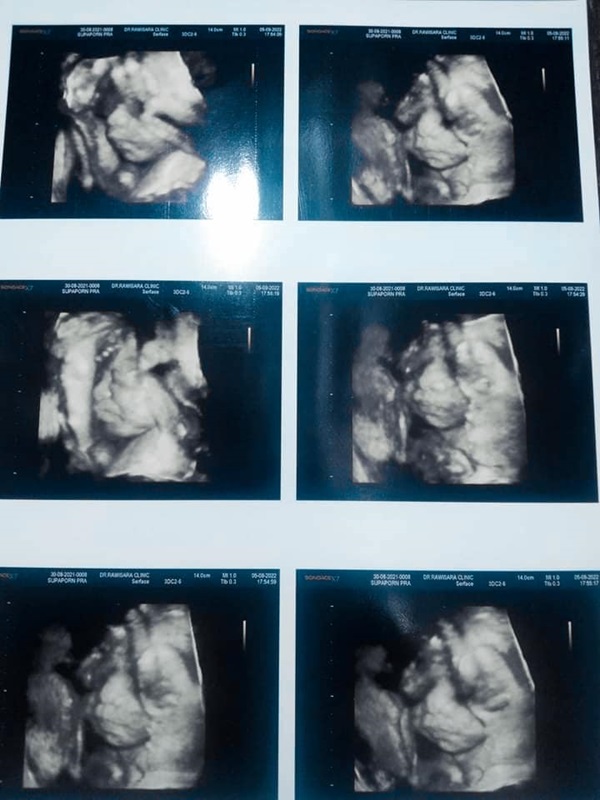

จากการตรวจสอบเฟซบุ๊กสามีของครูพี่เลี้ยงศูนย์พัฒนาเด็กเล็กตำบลอุทัยสวรรค์ พบว่ามีการโพสต์ภาพที่ถ่ายคู่กับคนรักเมื่อครั้งที่เรียนจบสวมชุดบัณฑิต ส่วนอีกภาพเป็นรูปการทำอัลตราซาวด์เพื่อดูลูกน้อยซึ่งอยู่ในครรภ์ภรรยา โดยสามีระบุว่า...